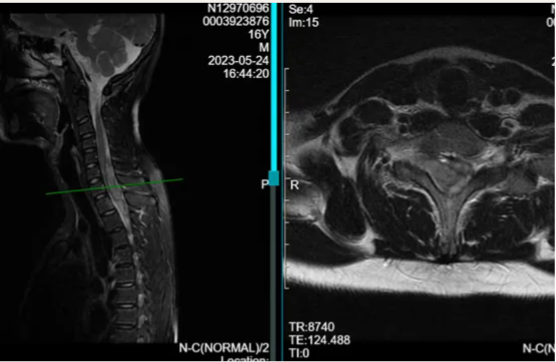

图:MRI表现为颈6-胸3水平脊髓内占位病变,T2像混杂高信号

辅助检查:MRI对脊髓海绵状血管瘤诊断有特异性,可显示不同时期出血成分的信号变化。病灶主要表现为T1和T2加权像呈混杂信号,病变周围可见含铁血黄素沉积形成的长T1短T2的低信号带,T2像最明显,典型者可呈“牛眼征”。